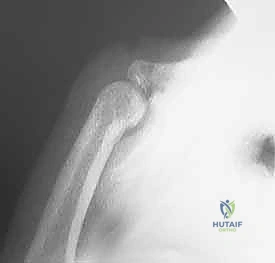

1. Initial Assessment and Reduction under Anesthesia

With the patient anesthetized and the tourniquet inflated, perform a final assessment.

- Palpation: Re-palpate the joint for any subtle deformities or instability.

- Stress Testing: Under fluoroscopic guidance, gently stress the joint to confirm the degree and direction of instability. This helps confirm your preoperative diagnosis and guides your reduction maneuver.

Your primary goal now is to achieve a concentric reduction of the PIP joint.

- Reduction Maneuver: Grasp the middle phalanx firmly. Apply gentle, sustained axial traction to disimpact the joint. While maintaining traction, hyperflex the PIP joint to 90 degrees or more. Simultaneously, apply direct volar pressure to the dorsal aspect of the middle phalanx base to reduce it back onto the proximal phalanx head.

- Fluoroscopic Confirmation: Immediately confirm concentric reduction with fluoroscopy in both AP and true lateral views. Ensure there is no residual subluxation or gapping.

Fluoroscopic confirmation of concentric reduction.

Surgical Warning: If concentric reduction cannot be achieved or maintained, even after repeated attempts, consider soft tissue interposition (e.g., a ruptured volar plate, collateral ligament, or even a small bony fragment). In such cases, an open reduction may be necessary to clear the joint. Be prepared to convert.